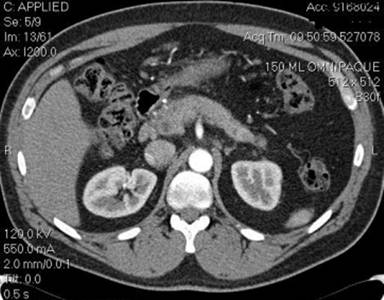

A follow-up CT six months later showed a significant decrease in the size of the pseudocyst (Figure 2). He was pain free and his liver function test at this time has returned to normal. The patient was instructed to continue taking ursodeoxycolic acid, prednisone and mycophenolate mofetil.

Figure 2. Complete resolution of the pseudocyst post procedure. |